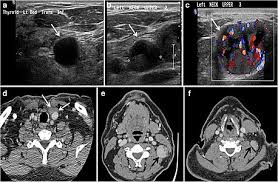

When evaluating a patient with a thyroid nodule, assessment of the lymph nodes, particularly in the lateral neck, provides important clues regarding the malignancy risk. In addition, the following tests may be used to diagnose head and neck cancer: Optimal positioning and exposure of the neck for ultrasound of the thyroid and parathyroid glands (a, b) and lateral neck for lymph node examination and mapping (c).while the vast majority of patients are supine on the exam table with a pillow supporting the shoulders to allow gentle neck extension, keep in mind that some patients have beautiful anatomy (d) that allows ultrasound exam even in. A biopsy can be performed in cases where ultrasound cannot differentiate benign from malignant tumours. Before the node starts the lesions even very experienced specialist, the device will be able to register an increase, its contour irregularity, violation of the structure.

Diagnosis Of Papillary Thyroid Cancer from www.thyroidcancer.com The image may or may not suggest cancer, but definitive diagnosis requires removal of. Surgical levels of the neck. It can detect abnormal tissues, growths, and cysts and give a suspicion of cancer based on how those images look. This test will usually help determine that the nodule has a low chance of being cancerous (has characteristics of a benign nodule), or that it has some characteristics of a cancerous nodule, and therefore a biopsy is indicated. Level i constitutes lymph nodes above the anterior and posterior bellies of the digastric muscle cephalad to the hyoid bone and inferior to the inferior border of the mandible and includes the submental group of nodes. Thyroid nodules that are hypervascular, hypoechioc, or contain calcifications on ultrasound are more likely to be malignant. Ultrasound does not show the structures inside joints, dr. A neck ultrasound may help diagnose (find):

Ultrasoundis very sensitive and showsmany nodules that cannot be felt. In addition, the following tests may be used to diagnose head and neck cancer: Ultrasound does not show the structures inside joints, dr. Fna might also be used in patients whose cancer has been treated by surgery and/or radiation therapy, to help find out if a neck mass in the treated area is scar tissue or if it's a return (recurrence) of the cancer. Ultrasound technology cannot find ulcers, but other types of diagnostic tests can. Some research explores the potential for finding ulcers with an ultrasound, but experts do not have enough data to recommend it. The path report states loose fragments of poorly differentiated malignant epithelial cells with enlarged hyperchromatic irregular nuclei and apoptosis are seen in a hemorragic background that includes few scattered atypical keratinized squamous cells. Testing lymph nodes the lymph nodes in the neck are often the first place cancer cells spread to outside the primary site. Ultrasoundimaging is a noninvasive medical test that helps physicians diagnose and treat medical conditions. If this lump is of concern then a biopsy would be the next step. Cancer of the liver or fatty. Optimal positioning and exposure of the neck for ultrasound of the thyroid and parathyroid glands (a, b) and lateral neck for lymph node examination and mapping (c).while the vast majority of patients are supine on the exam table with a pillow supporting the shoulders to allow gentle neck extension, keep in mind that some patients have beautiful anatomy (d) that allows ultrasound exam even in. Abnormal enlargement of the spleen.

Confirming that a lump in the neck is developing from the thyroid or connected tissue. The sonographer then gently presses the transducer against the side of your neck. Identification of a suspicious lymph node increases the likelihood of cancer and may warrant fna of the node in lieu of the thyroid (see fig. Surgical levels of the neck. This test will usually help determine that the nodule has a low chance of being cancerous (has characteristics of a benign nodule), or that it has some characteristics of a cancerous nodule, and therefore a biopsy is indicated. The ultrasound technician (sonographer) may position your head to better access the side of your neck. During a physical examination, the doctor feels for any lumps on the neck, lips, gums, and cheeks. Abnormal enlargement of the spleen. In my experience an ultrasound won't tell you if you have cancer, it just shows a lump. If cancer is found in a lymph node, you may need a neck dissection or other additional treatment. Doctors often use ultrasound to guide a needle to do a biopsy (taking out fluid or small pieces of tissue to be looked at under a microscope). Throat cancer is often easily seen by an ent exam. It can detect abnormal tissues, growths, and cysts and give a suspicion of cancer based on how those images look.